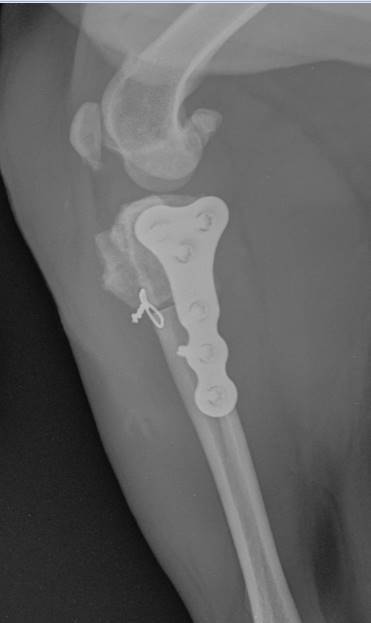

Cranial Closing Wedge Osteotomy (CCWO) is the universal surgery to manage canine cranial cruciate ligament disease. Suitable for dogs large and small, young and old it offers flexibility beyond any other tibial osteotomy technique.

In the morning session we cover the key objectives before practicing the technique on saw bone and then in the wet lab for a hands-on practical. Learn patient assessment, pre-operative planning, implant selection, instrumentation, postoperative care, and complication handling. Gain hands-on experience through dry and wet lab sessions for confident surgical execution.

• To understand the biomechanics of the cruciate ligament deficient stifle and cranial closing wedge osteotomy